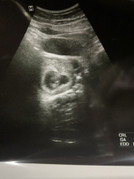

แม่ๆซาวด์เจอน้องตอนกี่วีคกันคะ บ้านนี้5w6D ยังไม่เจออะไรเลยค่ะ 🥹

เจอตอน5W6Dค่ะแม่ แต่ว่าน้องยังเล็กมากๆ เสียงหัวใจเป็นคลื่นเบาๆ

แม่ใจเย็นๆน้า บางคนเจอ 8 วีคยังมี เราเจอ 6 .4 วีคค่ะ

9w3dค่ะ ซาวผ่านหน้าท้อง👶🏻

6w6dค่ะ ทราบผ่านช่องคลอด

บ้านนี้ 6 วีคจ้า✌️

บ้านนี้6w3dเจอค่ะ

บ้านนี้7w ค่ะแม่

ของเราแต่แรกก็ไม่เจอจนจะ7วีคเจอแต่เล็กมากแต่หมอนัดซาวอาทิตย์ละครั้ง